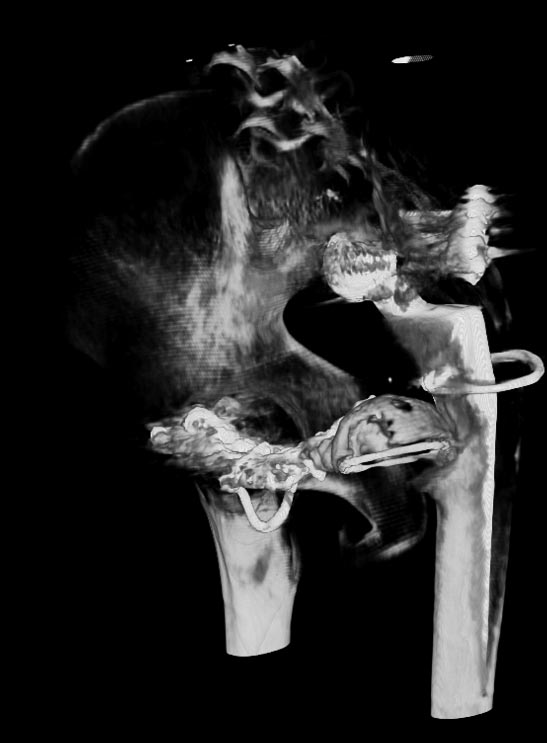

Мужчина 21 год, 2 года назад обнаружен эхиннокок костей таза, часть костей удалена сделано эндопротезирование и остеосинтез. Послеоперациооный период протекал гладко, через 6 месяцев упал, лечился консервативно, далее цепная реакция из проблем: гнойный остеомилит, свищи и лизис костей таза, на бак посеве эхинокок не обнаружен. Бедро не опорно, но больной предвигается на костылях. Картина маслом на рентгене и кт.об артродезировании думали, но диастаз большой, да и на фоне лизиса и остеопороза?????